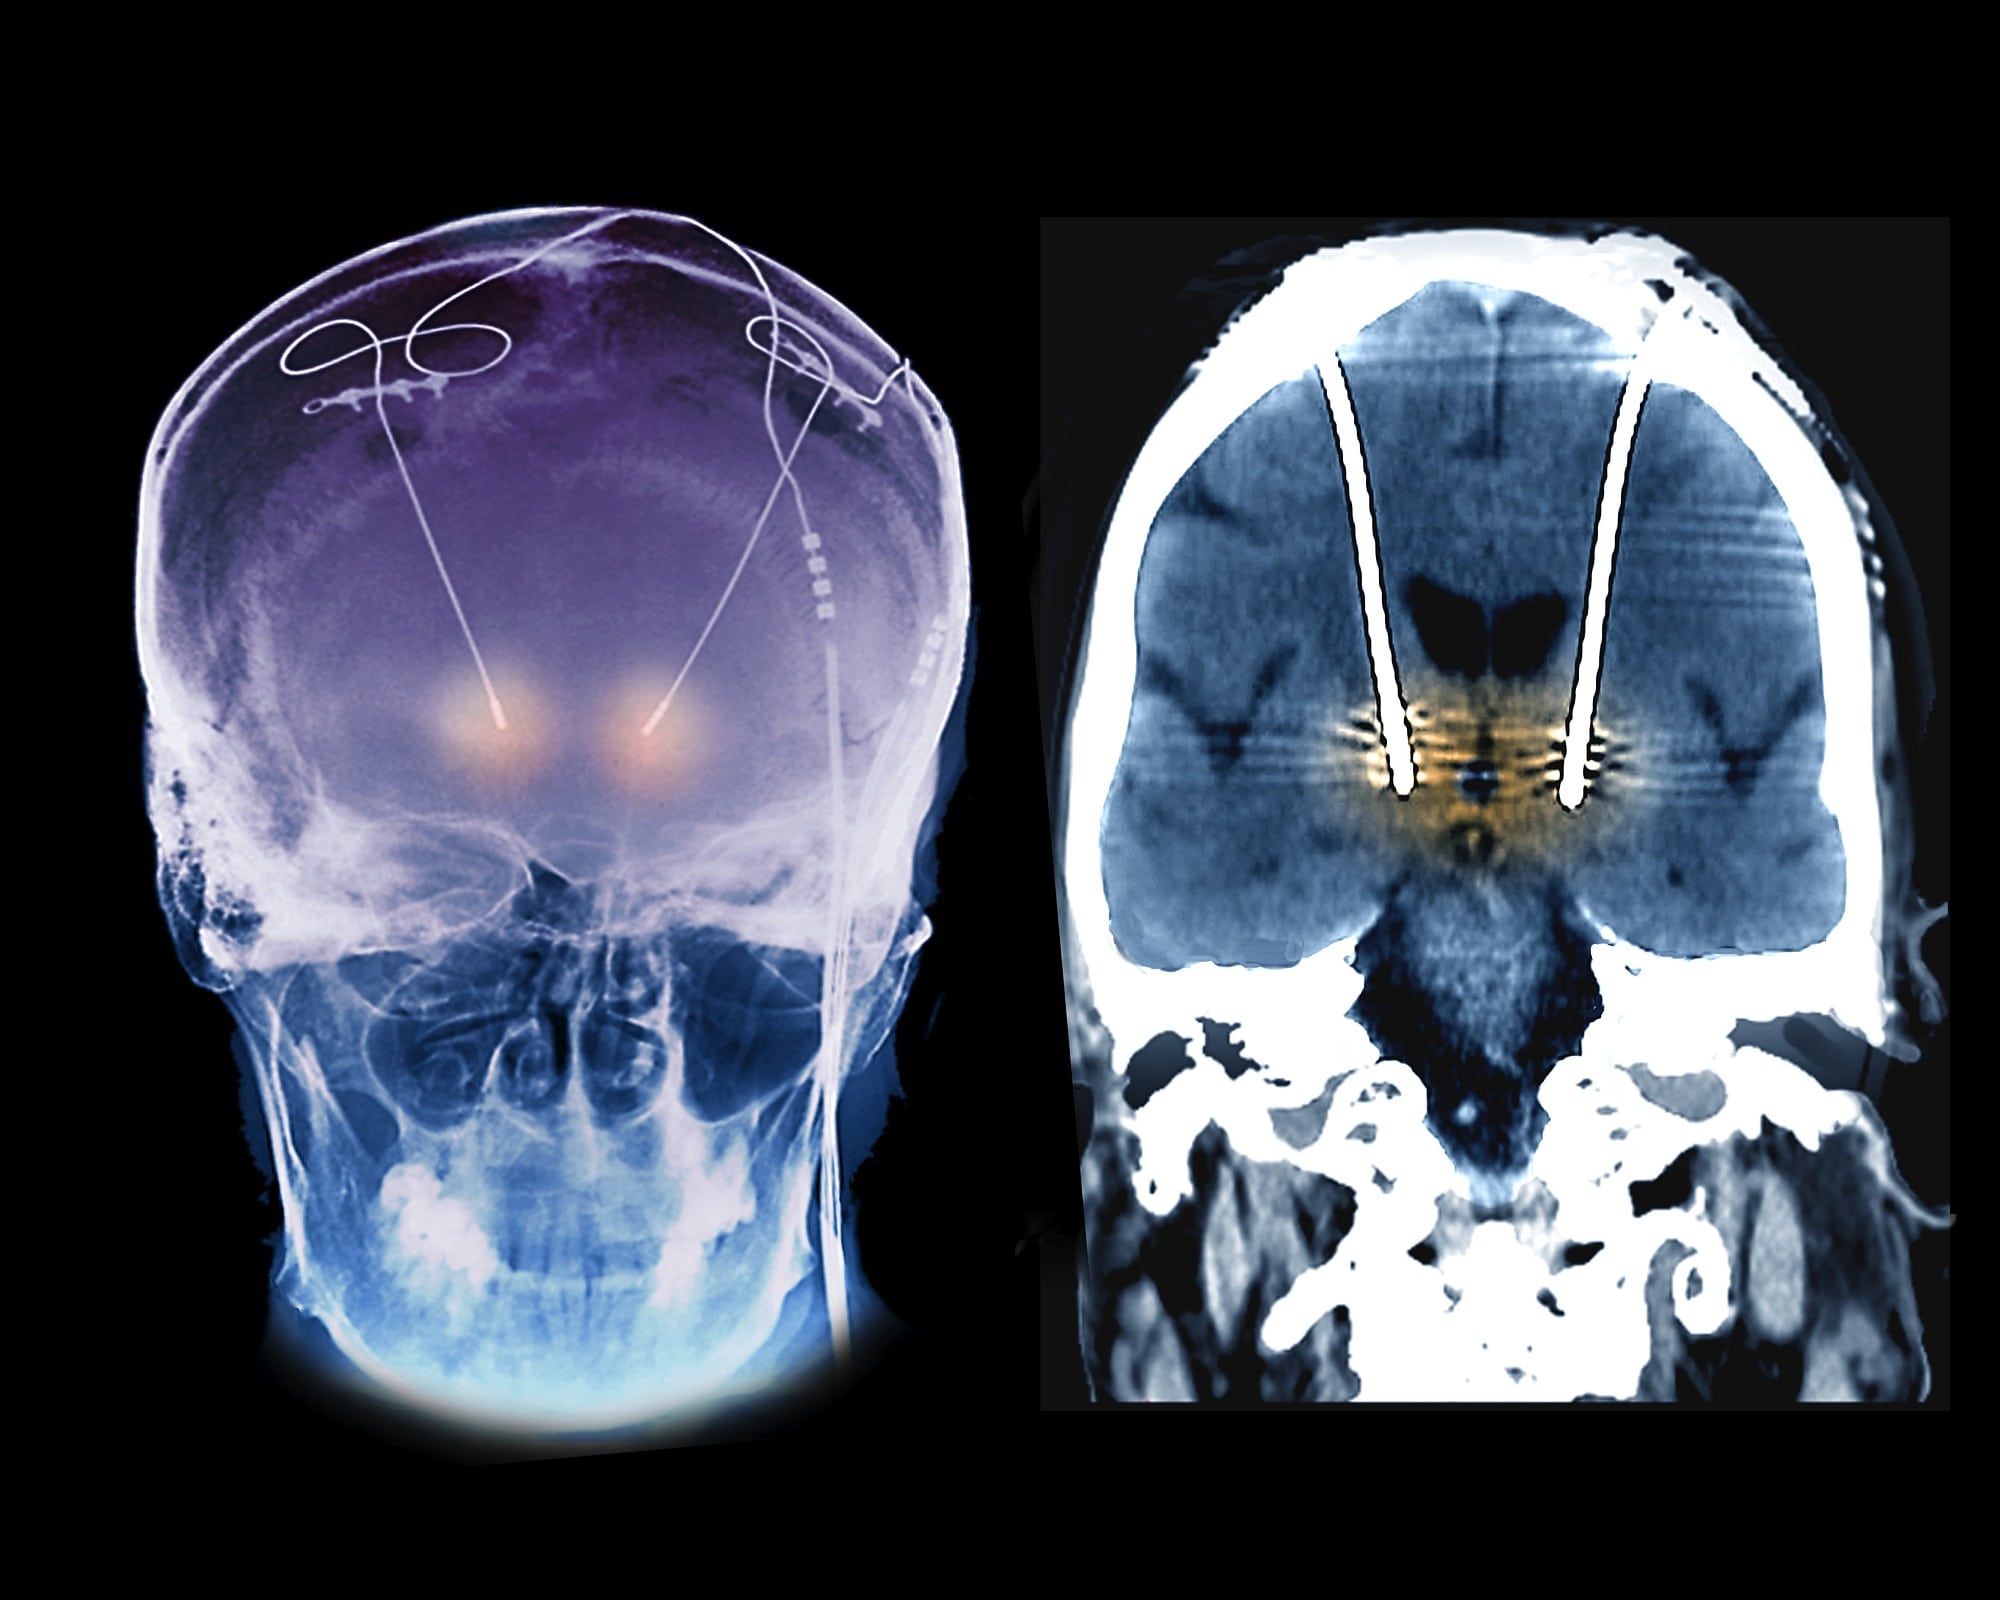

In den späten 1980er Jahren setzten französische Wissenschaftler Elektroden in das Gehirn von Parkinsonpatienten ein, bei denen die Krankheit schon weit fortgeschritten war. Elektrische Ströme in den mutmaßlich für das Zittern verantwortlichen Hirnarealen sollten dort die neuronale Aktivität unterdrücken. Vielen Betroffenen half diese tiefe Hirnstimulation enorm: Heftige und kräftezehrende Zitteranfälle ließen augenblicklich nach, sobald die Elektroden angeschaltet wurden.

1997 genehmigte die US-amerikanische Food and Drug Administration (FDA) die tiefe Hirnstimulation zur Behandlung von Parkinsonsymptomen. Seitdem wird die Methode bei diversen anderen Erkrankungen erprobt: Sie ist mittlerweile zur Therapie von Zwangsstörungen und Epilepsie zugelassen und wird für psychische Störungen wie Depression oder Magersucht getestet.

Die Symptome vieler Hirnerkrankungen tauchen unvorhersehbar auf. Deshalb kommen zunehmend Methoden zur Hirnüberwachung zum Einsatz. Solche Aufzeichnungselektroden – wie etwa bei Patientin 6 – verfolgen die Hirnaktivität, um zu erkennen, wann Symptome auftreten oder kurz bevorstehen. Doch statt lediglich dem Anwender einen Hinweis zu geben, senden manche autonom einen Befehl an eine Stimulationselektrode. Diese unterdrückt die relevante Hirnaktivität, sobald sich ein epileptischer Anfall oder bei Parkinsonpatienten ein Tremor abzeichnet. Einen derartigen geschlossenen Regelkreis hat die FDA bereits 2013 zur Behandlung von Epilepsie zugelassen; ähnliche Systeme zur Parkinsontherapie werden klinisch getestet.